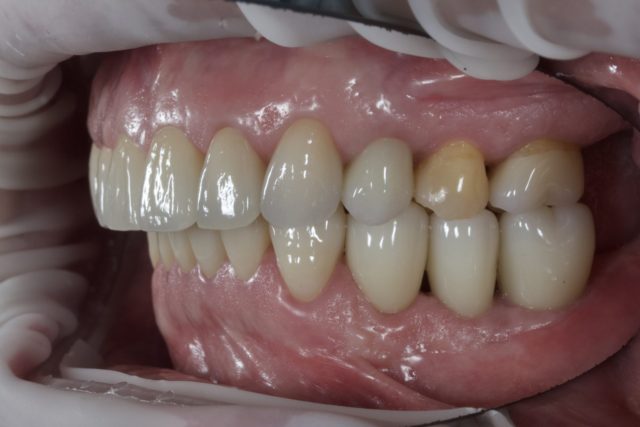

AFTER

| 備考 | 全体で問題が起こり機能が失われた状態をトータルでマネジメントし元あった理想に近い形に戻すことを行なっているが、これにはかなりの時間と費用がかかり、大変な治療に耐えていただく必要がある。 また全ては修復物や補綴物やインプラントで見た目と噛む機能を整えているに過ぎず、実際には歯が再生したわけではない。強度の落ちている歯をよく噛める形に整えるという事は、歯が壊れる可能性も同時に上げることになる。つまり施した治療が必ずしも一生保つという事ではない。 よって可能な限りこの状態を長く保つことが出来るよう、治療後は定期的なメンテナンスと、ナイトガード(寝ている間の歯軋りや食いしばりなどの自身でコントロールできない過剰な力から歯を守るマウスピース)の装着が必須となる。 |